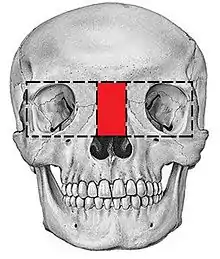

Hypertelorism

There are many types of operations which can be performed to treat a hypertelorism. 2 options are: box osteotomy and facial bipartition[26] (also referred to as a median fasciotomy). The goal of the box osteotomy is to bring the orbits closer together by removing a part of the bone between the orbits, to detach both orbits from the surrounding bone structures and move both orbits more to the centre of the face. The goal of the facial bipartition is not only to bring the orbits closer together, but also to create more space in the maxilla. This can be done by splitting the maxilla and the frontal bone, remove a triangular shaped piece of bone from the forehead and nasal bones and pulling the two pieces of forehead together. Not only will the hypertelorism be solved by pulling the frontal bone closer together, but because of this pulling, the space between the both parts of the maxilla will become wider.

Box Osteotomy

Box Osteotomy Facial Bipartition